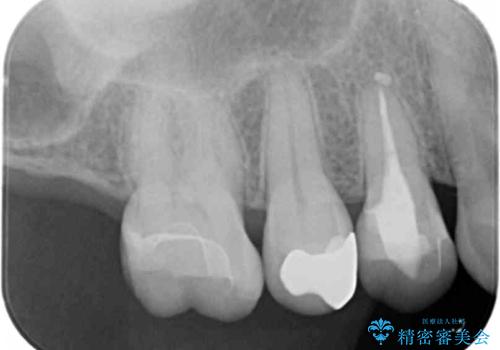

銀歯を白くしたい

- 銀の詰め物を白くしたいとのことで来院されました。

セラミックインレーでの治療を行いました。

- 右上5 セラミックインレー 77,000円×1本費用は治療当時の料金となります

残る歯の厚みが確保されている場合はインレーでの修復が可能です。